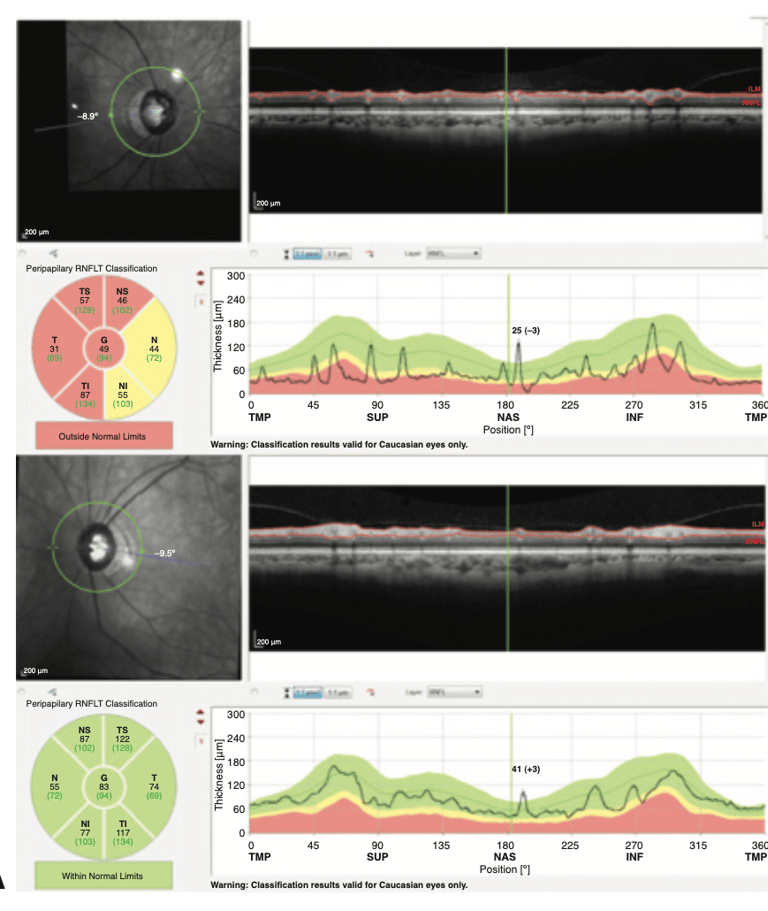

Tomografia de Coerência Óptica (OCT): Para examinar o nervo óptico em detalhes.

Tomografia de Coerência Óptica (OCT)